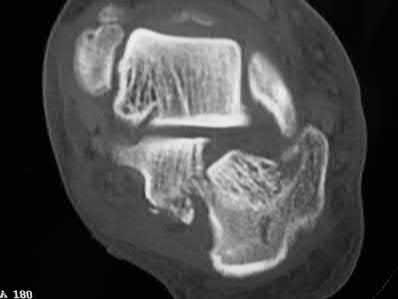

Figures A and B show a AO/OTA type C2 intraarticular distal humerus fracture. Figure C is a coronal CT scan showing intraarticular comminution. Illustration A shows fixation of the fracture with bicolumnar plating through an olecranon osteotomy approach. Illustration B shows the various approaches to the distal humerus (left, Campbell triceps splitting; center left, O'Driscoll triceps reflecting anconeus pedicle; center right, Bryan-Morrey approach, leaving the triceps attached laterally to the fasciocutaneous flap, but elevating it off the ulna; right, olecranon osteotomy). Illustration C shows 3 methods of olecranon osteotomy (A and B, Intra-articular transverse; C-F, Extra-articular oblique; G, Intra-articular chevron).